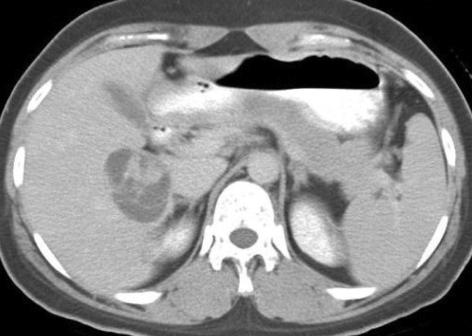

A primary benign schwannoma of the liver is extremely rare. Only nine cases have been reported in the medical literature worldwide and no case has been reported in Korea previously. A 36-yr-old woman was admitted to our hospital with vague epigastric pain. The ultrasound and computed tomography scan revealed a multi-septated cystic mass in the right lobe of the liver. The mass was resected; it was found to be a 5 x 4 x 2 cm mass filled with reddish yellow fluid. The histological examination confirmed the diagnosis of a benign schwannoma, proven by positive immunoreaction with the neurogenic marker S-100 protein and a negative response to CD34, CD117 and smooth muscle actin. This is the first report of a benign schwannoma of the liver parenchyma in a Korean patient.

原发性肝脏良性神经鞘瘤极为罕见。全球医学文献中仅报道过9例,韩国此前尚无相关病例报告。一名36岁女性因上腹部隐痛入院。超声和计算机断层扫描显示肝脏右叶有一个多分隔的囊性肿块。该肿块被切除,发现是一个5×4×2厘米的肿块,充满红黄相间的液体。组织学检查证实为良性神经鞘瘤,通过与神经源性标志物S-100蛋白的阳性免疫反应以及对CD34、CD117和平滑肌肌动蛋白的阴性反应得以证实。这是韩国患者肝脏实质良性神经鞘瘤的首例报告。